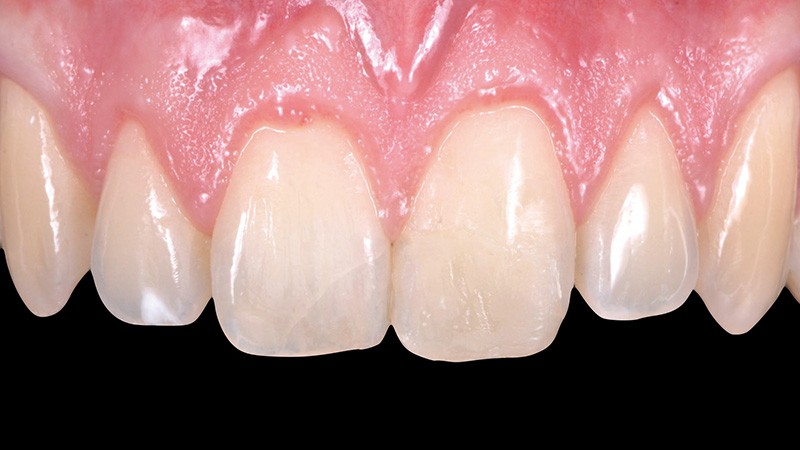

5. Situation à une semaine. La couleur et la forme s’intègrent bien…

6. …mais le travail sur l’état de surface fait clairement défaut. En réalité, la séance de contrôle à une semaine permet d’apporter les éventuelles retouches de teinte ou de forme ou, si besoin, de combler une porosité de surface. Il serait donc contre-productif de travailler la texture de surface dès la première séance.